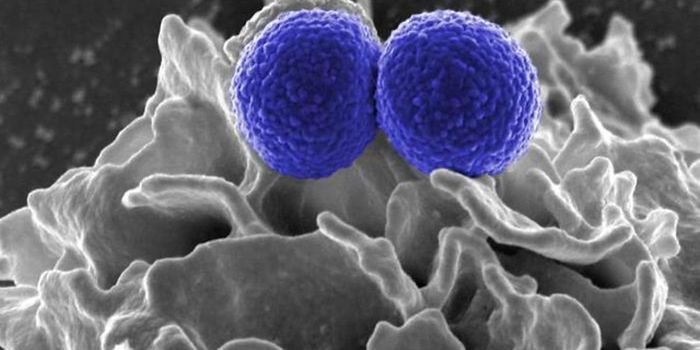

SEP 17, 2021Cell & Molecular BiologyMRSA (methicillin-resistant Staphylococcus aureus) is a well known superbug, a pathogenic microbe that can cause serious ...